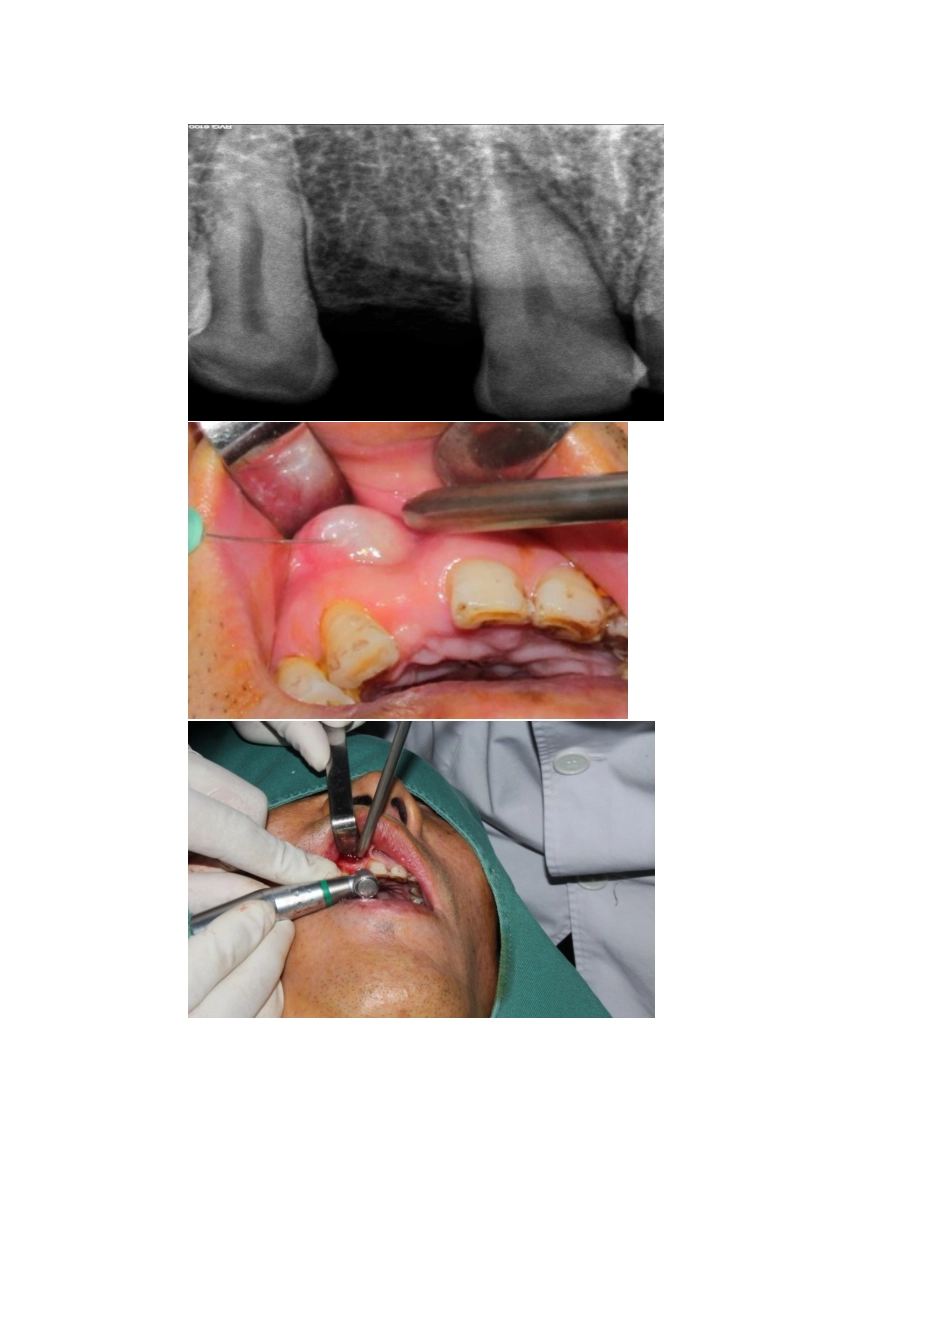

我院口腔牙科成立于上世纪50年代,是集口腔内科、口腔外科、口腔修复、口腔正畸为一体的综合性科室,技术水平一直在我县处于领先地位。科室现有副主任医师1人、主治医师1人、医师5人,科室人员先后在河南省口腔医院、郑州大学第一附属医院进修学习,技术力量雄厚。配备有德国FONA牙科综合治疗机6台,德国卡瓦口腔种植机一台、牙片X光机、超声波洁牙机、齿科打磨机、齿科成型机、点焊机等设备。所有诊疗器械医院供应室集中消毒、灭菌,做到“一人一用一灭菌”,严格杜绝感染病的感染隐患,保障患者就诊的卫生与安全。为患者提供安全、舒适的治疗。口腔修复与种植优势技术口腔修复科主要是对牙体缺损、牙列缺损、牙列缺失和畸形的患者进行修复治疗,俗称镶牙。目前修复的方法很多,有活动修复,固定修复,种植体修复。种植牙是目前公认的最好的修复方法,被称为人类的第三副牙齿。1种植牙种植牙是目前口腔修复领域最先进的技术,它具有变革性的意义,对口腔医学的医疗行为和模式产生了深刻的影响,被喻为除乳牙和恒牙以外的“第三副牙齿”。种植牙是通过小手术将纯钛的种植体植入患者的牙槽骨内,形成人工牙根,然后在种植体上安装假牙冠的一种修复方法。它适用于口腔内单个牙、多个牙和全口牙齿的缺失。传统的固定、活动修复方法都需要依靠其它自然牙来达到假牙的固位,而种植牙因为有人工牙根,具有类似于自然牙的支持方式和仿生学的优势,它不需要像固定牙那样对缺失牙两边的牙齿进行磨除,同时具有美观、自然、舒适、咀嚼功能恢复好等优点,使患者在心理上认为等同于长出了新的牙齿,对提高患者的生活质量、树立交往的自信心有很好的帮助。种植牙对患者的选择比较严格,患者要身体健康,无全身疾病,另外口腔局部的骨量和骨质要符合要求。另外,它治疗周期相对较长,费用相对于其他修复方法昂贵,并要求患者与医生有良好的配合,才能取得良好的效果。我科最新引进的德国卡瓦口腔种植机,是当前牙齿缺失修复领域中最先进,最经典的种植系统。德国种植机采用的是世界最顶级种植体,被业内人士称为“贵族专享种植体”种植过程:第一次:口腔检查。包括:口内检查;拍X光片了解牙槽骨情况;特殊情况下需拍CT检查;术前的手术及修复设计;模型分析、制作手术导板;预约手术时间;血常规检查;全口腔洁治;第二次:一期手术植入种植体;第三次:拆线。一期手术后7-10天拆线,拍片了解种植体植入情况;第四次:二期手术。一期手术3-6个月后进行二期手术,安装愈合基台使牙龈形成,需拍片了解种植体骨整合情况;第五次:种植修复取模。二期手术后2星期取模,安装修复基台,根据情况有时需拍片;第六次:种植义齿戴牙(戴牙后需拍片)术前及术中:2.全瓷修复技术全瓷牙是指由陶瓷材料制作的人工牙冠。它适用于牙冠缺损,或牙体变色、氟斑牙、四环素牙。由于全瓷牙的颜色和光学性质与自然牙十分近似,其美观效果最佳,尤其适用于患者牙齿不好看,欲改善牙齿的外观、颜色等情况,修复后可以达到以假乱真的效果。全瓷牙根据材料不同有许多种类,如铸瓷牙、氧化锆全瓷牙等。口腔正畸技术口腔正畸科主要治疗各年龄段患者的个别牙齿错位、牙齿排列异常、牙弓形态异常、前牙深覆颌、深覆盖、反颌、上下颌前突等错颌畸形。我们矫治的患者除儿童外,成人患者也很多。活动矫治:一般常用于乳牙和替牙期的比较简单的错和畸形的矫正,或者配合固定矫治器进行矫治。病人自己可以摘戴地包天矫治一例:固定矫治:最为常用的矫治器。患者自己不能摘戴。固定矫治是在本世纪发展起来的正畸技术,其技术也日益成熟,与活动矫治器比较,固定矫治器粘贴在牙齿表面上,所以固位良好;病人不能自行取下,可使矫治力得以持续发挥,因而疗程短,复诊间隔时间长;矫治较复杂的牙颌畸形效果好。固定矫治一例:我科医务人员重视吸取国内先进的治疗技术,如方丝弓矫治技术、MBT矫治技术、成人各类错颌的正畸治疗以及儿童各类畸形的功能矫治技术口腔内科特色技术口腔内科主要治疗牙体病、牙髓病、牙周病、口腔粘膜病。1.残冠利用技术近年来,龋病、牙髓病的治疗理念、治疗方法、检查手段、充填材料、治愈标准都和传统的方法发生了很大变...